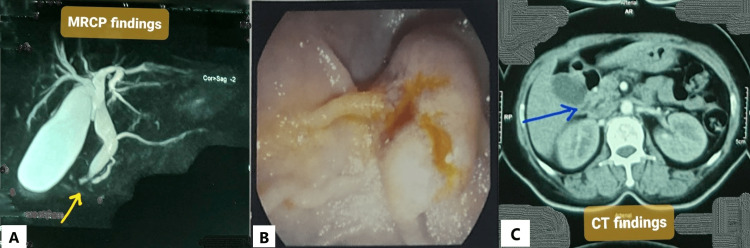

A magnetic resonance cholangiopancreatography (MRCP) was done, and it showed a distended gallbladder with calculi and sludge, as well as dilated CBD and MPD (double-duct sign) (Figure 1A). A UGI endoscopy was done to check the ampullary region. During the procedure, the ampulla was found to be swollen and ulcerated (Figure 1B). A forceps biopsy was obtained from the ampulla. Histopathology revealed that lamina propria in some areas contained signet ring cells, and some glands were lined by atypical epithelium, indicating adenocarcinoma, grade II. A review of the histopathology revealed similar malignant findings. To stage the disease, contrast-enhanced computed tomography (CECT) of the chest and abdomen was performed. It revealed an ill-defined, minimally enhancing soft tissue lesion in the periampullary area, similar to prior investigations (Figure 1C). The lesion caused biliary tree dilatation as well as mild pancreatic duct dilatation. The positron emission tomography scan was postponed due to the low socioeconomic condition of the patient.